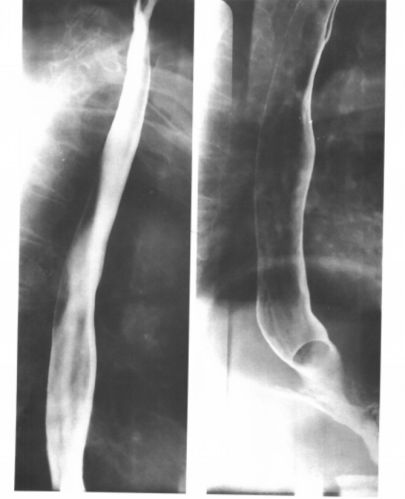

消化道内镜在食管疾病诊断得到广泛应用,使得食管疾病的诊断更加直接,但内镜检查是一种有创操作,并不是每个人都能接受。 钡餐造影在食管疾病依然有着独特的作用,能够反映食管管腔内病变,动态观察、反映器官功能状态。同时,相比于内镜,大大减少病人的痛苦;相比于CT,使得病人接受的放射线剂量大大减少。 在我们实…